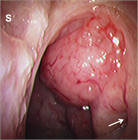

1. 扁桃肥大(アデノイド肥大を含む)は小児の睡眠時無呼吸(obstructive sleep apnea:OSA)を含む閉塞性睡眠時呼吸障害(obstructive sleep-disordered breathing:oSDB)の最も一般的な原因であり、このような小児患者に口蓋扁桃摘出術 ± アデノイド切除術は非常に有効である。一方、扁桃肥大は成長とともに軽減すること、術後出血などの術後合併症もみられることから、手術適応は慎重に評価しなければならない。成人の扁桃肥大では腫瘍性病変の可能性を念頭に置いて診断を進める必要がある。